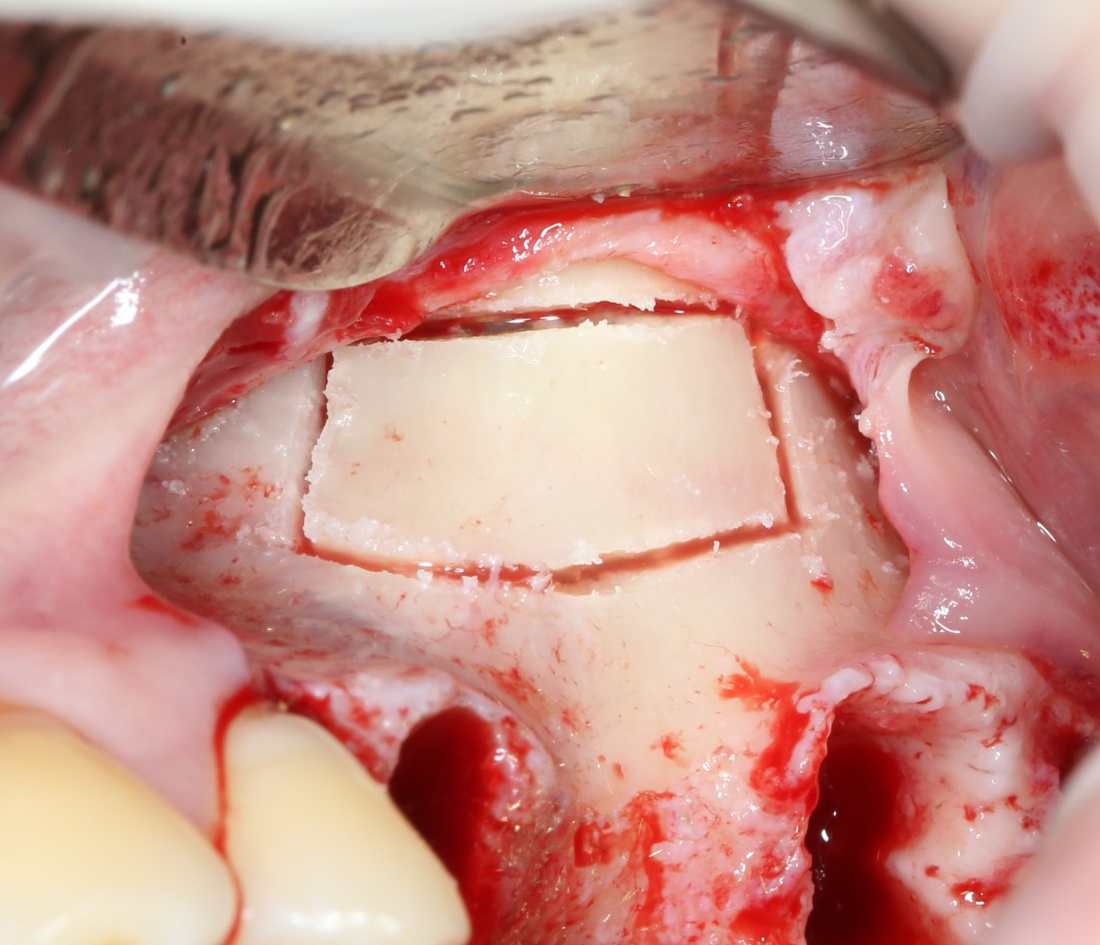

Вариант #2. Использование аутокостного фрагмента и/или свободного деэпителизированного лоскута.

Однако, при «костнопластическом» создании доступа в верхнечелюстную полость, у нас остается аутокостный фрагмент, который мог бы использоваться для закрытия случайной перфорации слизистой оболочки верхнечелюстной пазухи. Сделать это очень просто:

Минус у этого варианта один: он работает только в случаях «костнопластического» создания апертуры, когда у нас появляется «лишний» фрагмент аутокости. Если же доступ в верхнечелюстную полость создавался другим способом, то получение деэпителизированного лоскута потребует донорского участка, что, в свою очередь, увеличивает время и травматичность операции.